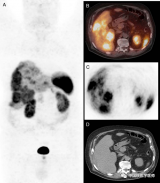

李锋:68Ga-DOTANOC PET/CT发现多灶性肝细胞癌

68Ga-DOTANOC PET/CT显像提示富血管肝脏病变表达生长抑素受体(SR),考虑为该病变为神经内分泌肿瘤,但后来确诊为肝细胞癌(HCC)。由于HCC病变在CT表现为富血管化,可类似神经内分泌肿瘤征象。虽然目前SR-PET/CT成像的适应症中不包含HCC,但在解读神经内分泌肿瘤患者的图像时,可能因HCC造成误诊。SR显像在HCC的诊断价值用仍需要进一步研究证实。 2022-06-05 核医学PET/CT